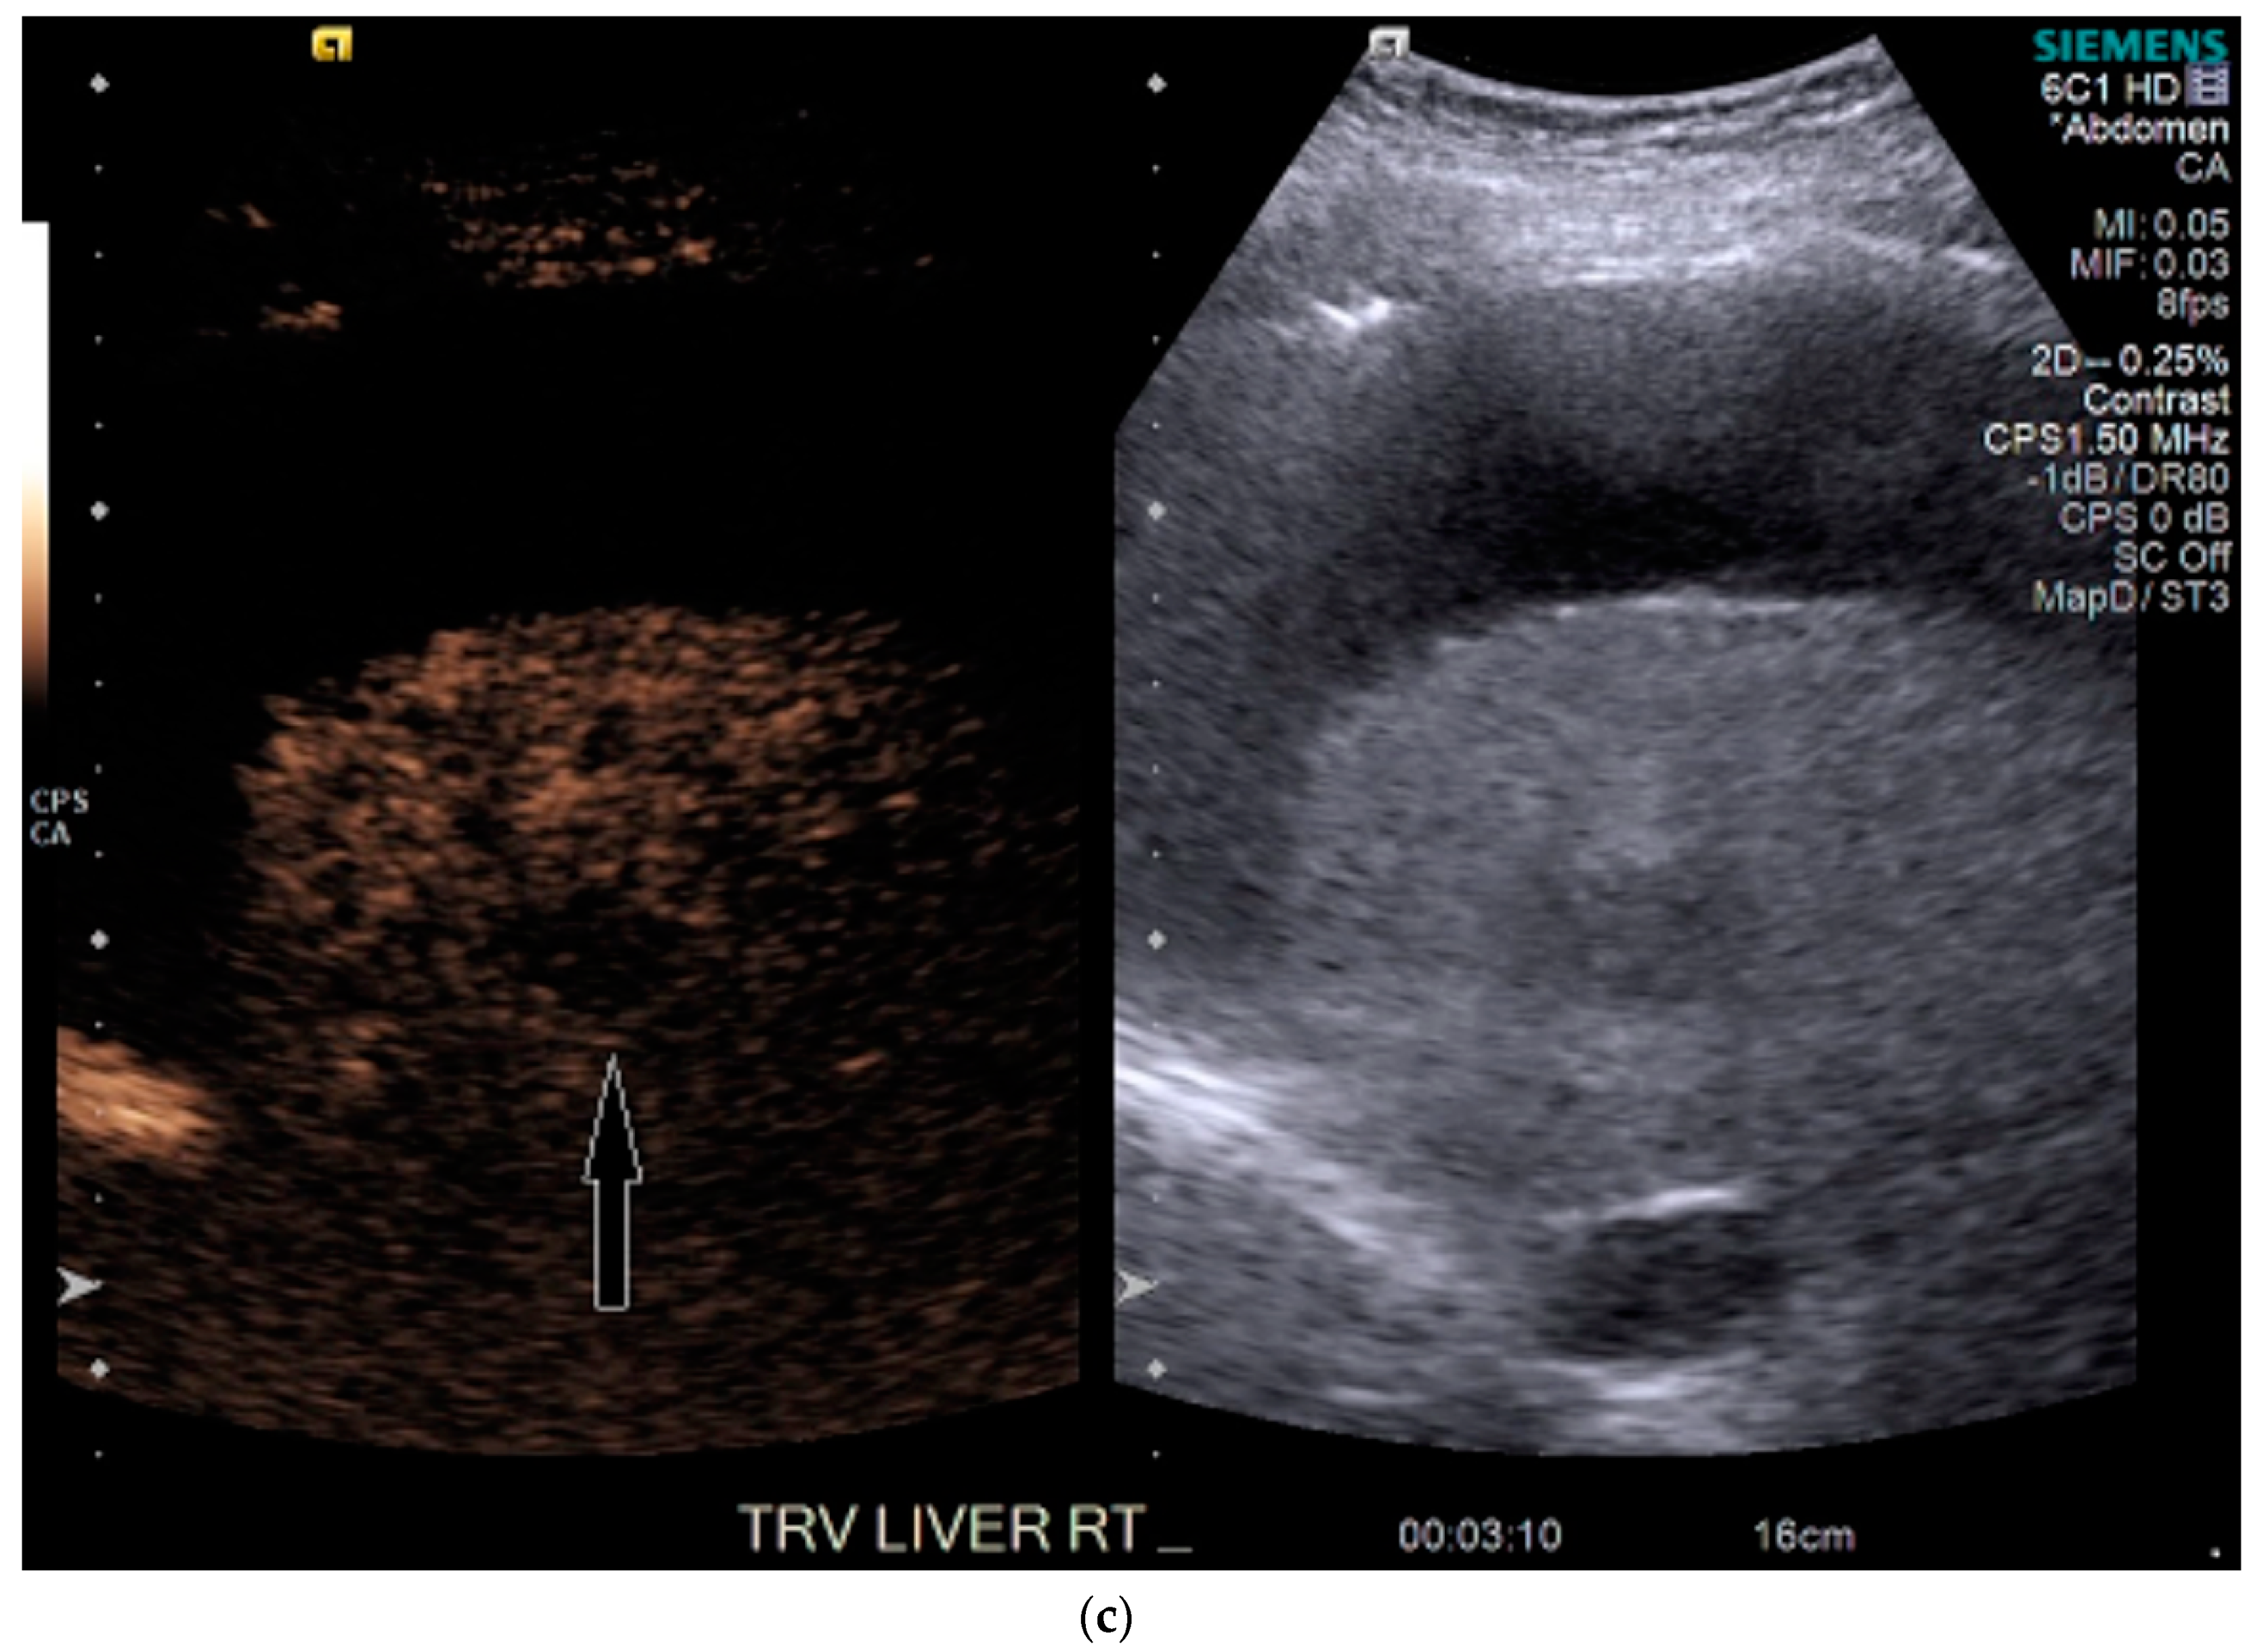

3.2. Case 2